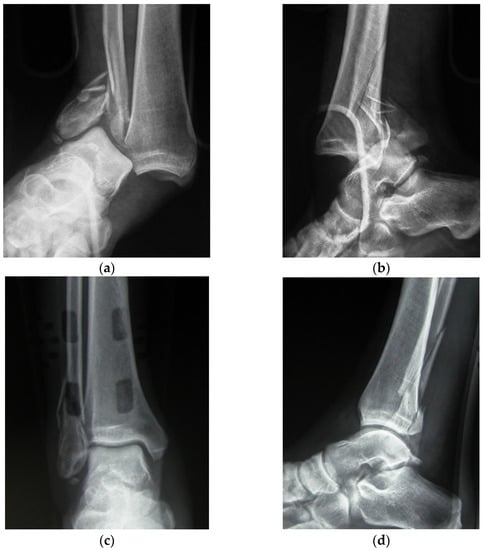

| Case | Sex—Age | Side | Energy | Type of Fracture | Weber Classif. | Quality of Reduction | Follow-Up Years | AOFAS | Radiograp. Results (Van Dijk) |

|---|---|---|---|---|---|---|---|---|---|

| 1 | M—20 | R | High | Unimal. | B | Good | 4.6 | 88 | 0 |

| 2 | F—51 | R | High | Unimal. | C | Excellent | 6.8 | 92 | 0 |

| 3 | F—39 | R | High | Bimal. | B | Good | 6.6 | 84 | 0 |

| 4 | F—77 | R | Low | Bimal. | C | Good | 4.2 | 92 | 1 |

| 5 | F—59 | R | High | Trimal. | B | Good | 4.6 | 96 | 1 |

| 6 | M—45 | R | High | Unimal. | A | Excellent | 4.2 | 84 | 0 |

| 7 | M—35 | L | High | Bimal. | B | Excellent | 5.3 | 88 | 0 |

| 8 | F—68 | R | Low | Bimal. | B | Excellent | 5.8 | 90 | 1 |

| 9 | F—26 | R | High | Bimal. | B | Excellent | 3.9 | 98 | 0 |

| 10 | F—79 | R | Low | Unimal. | C | Good | 4.8 | 85 | 1 |

| 11 | F—49 | L | High | Bimal. | B | Good | 5.2 | 75 | 1 |

| 12 | M—59 | R | High | Bimal. | C | Excellent | 5.5 | 92 | 0 |

| 13 | M—32 | R | High | Bimal. | B | Excellent | 5.3 | 82 | 0 |

| 14 | M—24 | R | High | Unimal. | B | Excellent | 6.8 | 80 | 0 |

| 15 | F—16 | R | High | Unimal. | C | Excellent | 3.7 | 96 | 0 |

| 16 | F—45 | R | High | Trimal. | B | Good | 5.9 | 88 | 0 |

| 17 | F—71 | R | Low | Trimal. | B | Good | 5.9 | 93 | 1 |

| 18 | M—45 | L | High | Unimal. | B | Excellent | 3.8 | 85 | 0 |

| 19 | F—24 | R | High | Bimal. | C | Excellent | 4.8 | 84 | 0 |

| 20 | F—66 | R | Low | Trimal. | B | Excellent | 5.2 | 92 | 0 |

| 21 | M—50 | R | High | Unimal. | C | Excellent | 6.1 | 94 | 0 |

| 22 | F—45 | L | High | Unimal. | B | Good | 4.9 | 86 | 1 |

| 23 | M—28 | R | High | Bimal. | C | Good | 5.6 | 76 | 1 |

| 24 | F—74 | R | Low | Trimal. | B | Good | 6.2 | 88 | 1 |

| 25 | F—28 | R | High | Unimal. | C | Excellent | 5.9 | 94 | 0 |

| 26 | F—62 | R | High | Bimal. | C | Good | 4.4 | 85 | 1 |